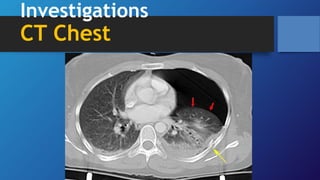

Investigations

CT Chest

•CT chest may be

required to

differentiate

pneumothorax from

bullous disease and is

useful in diagnosing

unsuspected

pneumothorax

following trauma and

in looking for evidence

of underlying lung

disease

Investigations CT Chest •CT chestmay be required to differentiate pneumothorax from bullous disease and is useful in diagnosing unsuspected pneumothorax following trauma and in looking for evidence of underlying lung disease